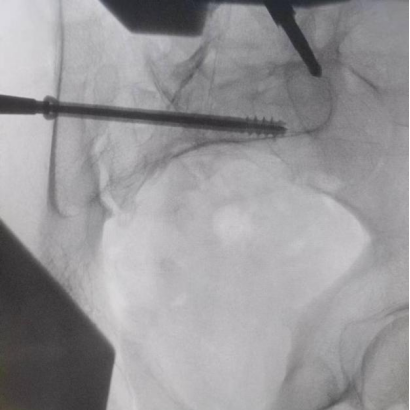

圖為透視下見置入的骶髂螺釘,位置、長度精準,無絲毫偏差